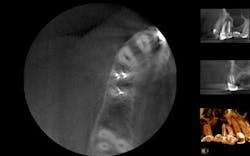

A 50-year-old male presented to my office on referral from his general dentist for evaluation of a large, periapical radiolucency relating to Nos. 4 and 5. Appropriate bitewing and peri-apical radiographs were taken (Fig. 1) for initial evaluation. After all clinical testing was performed, the recommendation was made to take a narrow-field CBCT image of teeth Nos. 4 and 5 (Figs. 2 and 3). The axial view reveals an untreated buccal canal on tooth No. 4 and potential separated instruments in both the buccal and palatal canal space of No. 5. Tooth No. 5 (Fig. 3) shows a short fill, meaning the entire canal space may not have been properly shaped and cleaned. With the three-dimensional images, we now have a better understanding of why these teeth present with post-treatment disease. This information is extremely important when discussing etiology and prognosis with our patients. It will also financially benefit the patient to maintain his existing fixed prosthesis with conservative retreatment of Nos. 4 and 5, knowing that we should have a high degree of long-term success seeing a clear etiology of the post-treatment disease.

Fig. 3: CBCT sagittal view